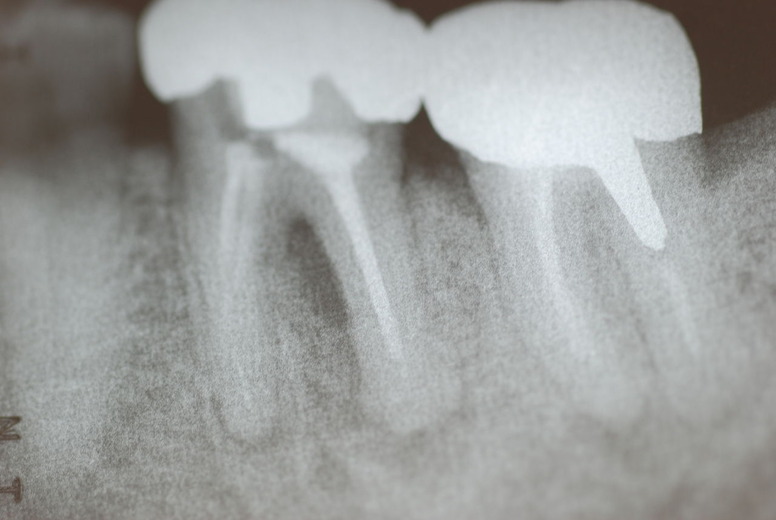

写真左下の親知らずが痛くなり抜歯しました。その後歯茎を除去して虫歯を露出させる処置を二回ほどしています。

レントゲンでは小さいですが、こう言う虫歯が一番怖いのです。

治療の成功率は極めて悪くすぐ再発しやすいのです。